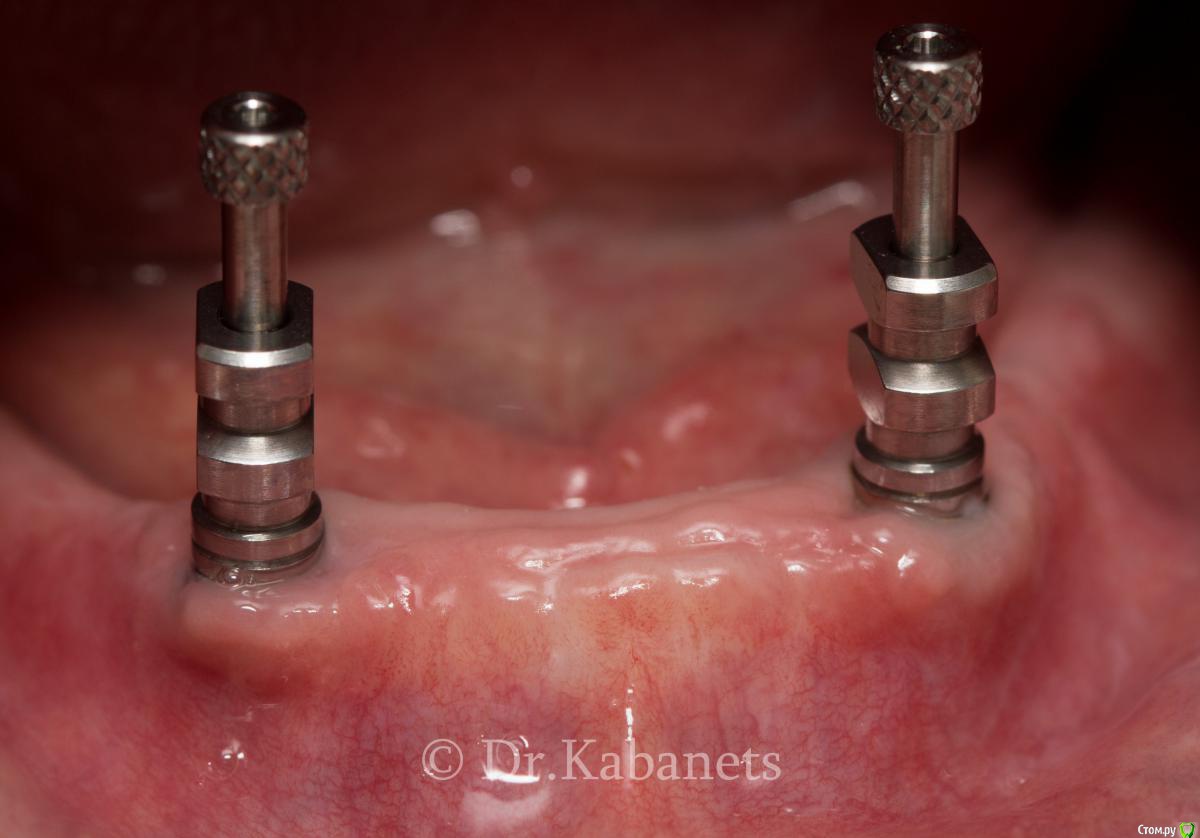

KIS Опубликовано 12 мая, 2015 Поделиться Опубликовано 12 мая, 2015 План:ВЧ: ПСПП НЧ: ПСПП с фиксацией на шаровидных титановых абатментах. Имплантаты AlphaBio. Коллеги, поделитесь опытом. Как вы измеряете высоту будущих абатментов? Суть вопроса:По вестибулярной поверхности высота 3мм. По язычной 4мм. Какой лучше выбрать, 3х миллиметровый или 4х? Ссылка на комментарий

chernov Опубликовано 12 мая, 2015 Поделиться Опубликовано 12 мая, 2015 (изменено) План:ВЧ: ПСПП НЧ: ПСПП с фиксацией на шаровидных титановых абатментах. Имплантаты AlphaBio. Коллеги, поделитесь опытом. Как вы измеряете высоту будущих абатментов? Суть вопроса:По вестибулярной поверхности высота 3мм. По язычной 4мм. Какой лучше выбрать, 3х миллиметровый или 4х?Инструкцию прочитай-поймёшь! Цитата из тех.руководства:"следует измерить толщину мягких тканей, при этом если уровень деснынеодинаков с разных сторон имплантата, ориентироваться следует по наибольшемузначению" Изменено 12 мая, 2015 пользователем chernov 1 Ссылка на комментарий

Dr.Zoom Опубликовано 12 мая, 2015 Поделиться Опубликовано 12 мая, 2015 План:ВЧ: ПСПП НЧ: ПСПП с фиксацией на шаровидных титановых абатментах. Имплантаты AlphaBio. Коллеги, поделитесь опытом. Как вы измеряете высоту будущих абатментов? Суть вопроса:По вестибулярной поверхности высота 3мм. По язычной 4мм. Какой лучше выбрать, 3х миллиметровый или 4х?абатменты 5 мм. если ровно 4, то край титановой втулки будет травмировать десневой край. Если бюджет позволяет, то лучше на локаторах. Ссылка на комментарий